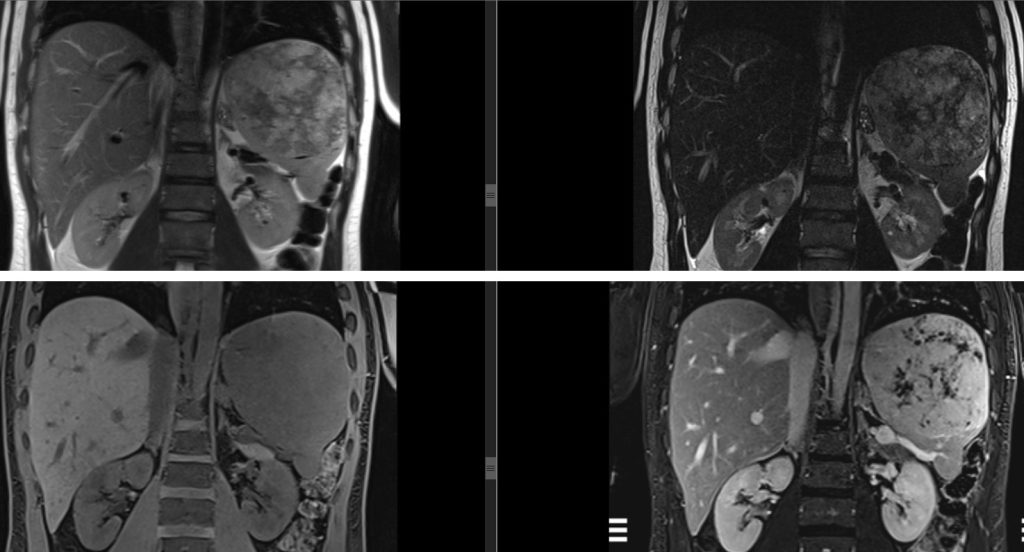

Figura 5: imagini în plan coronal T2 și coronal T1 pre si postcontrast în ponderatie T2 din achiziție IRM abominală superioară cu substanță de contrast